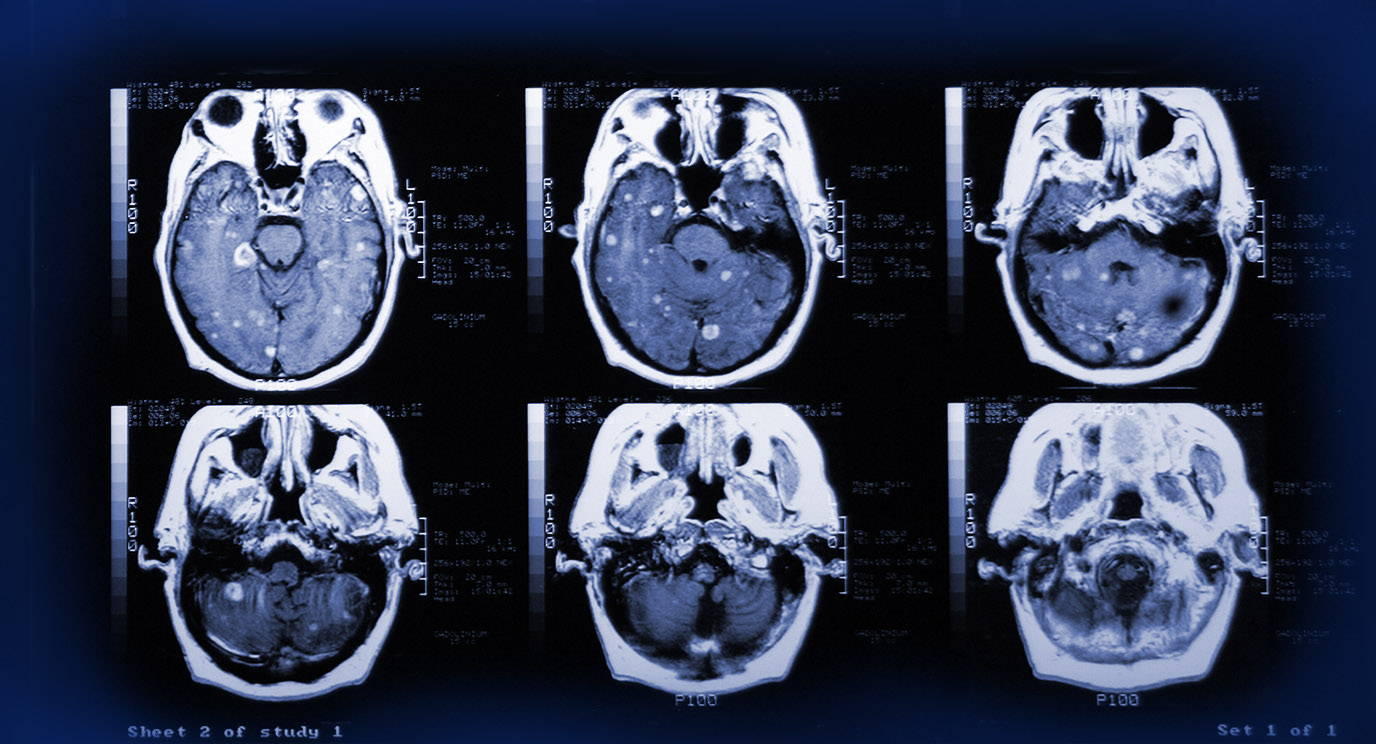

pulsatile erlotinib in egfr positive non small cell lung cancer patients with leptomeningeal and brain metastases review of the literature clinical lung cancer

https www oncologynurseadvisor com home headlines conference coverage esmo 2019 neurologic deficits shorten overall survival in nsclc with brain metastases at diagnosis